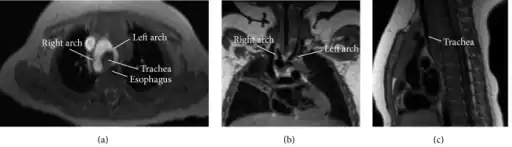

Double aortic arch is a relatively rare congenital cardiovascular malformation. DAA is an anomaly of the aortic arch in which two aortic arches form a complete vascular ring that can compress the trachea and/or esophagus.[1][2] Most commonly there is a larger (dominant) right arch behind and a smaller (hypoplastic) left aortic arch in front of the trachea/esophagus. The two arches join to form the descending aorta which is usually on the left side (but may be right-sided or in the midline). In some cases the end of the smaller left aortic arch closes (left atretic arch) and the vascular tissue becomes a fibrous cord. Although in these cases a complete ring of two patent aortic arches is not present, the term ‘vascular ring’ is the accepted generic term even in these anomalies.

Computed tomography (CT): Computed tomography after application of contrast media is usually diagnostically accurate. It shows the relationship of the arches to the trachea and bronchi.

Magnetic resonance imaging (MRI): Magnetic resonance imaging provides excellent images of the trachea and surrounding vascular structures and has the advantage of not using radiation for imaging compared to Computed tomography.